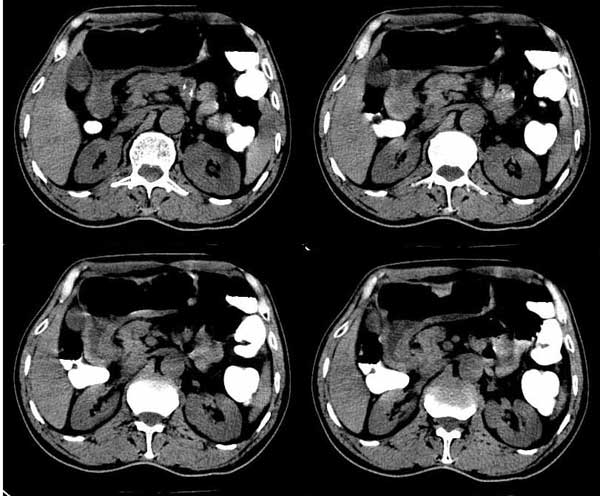

m/76 患者于2个多月前无明显诱因出现解肉眼血尿,为淡暗红色,无尿急、尿痛、脓尿,自服中草药后症状缓解

膀胱内高密度ct值约62hu

膀胱内偏右后方附壁见不规则软组织密度块影,边缘有分叶,综合患者症状考虑膀胱癌。

病人左肾有问题吗?肾皮质看上去很厚!

本人首先考虑膀胱内血凝块!跟踪临床经膀胱镜检查证实,但另有发现:膀胱冲洗血凝块后发现右侧壁见菜花样物质。

患者行膀胱镜检查,将血块冲洗后发现有菜花样物质! 当时完全被血块掩盖了!

今天下午病理出来了,是膀胱移行细胞癌